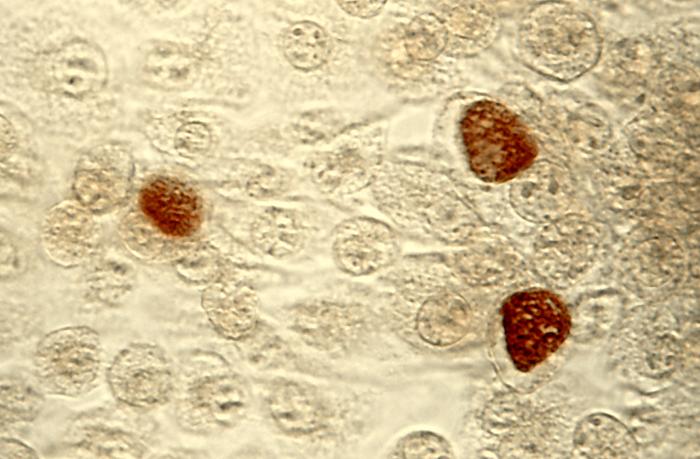

【クラミジア】wikipedia